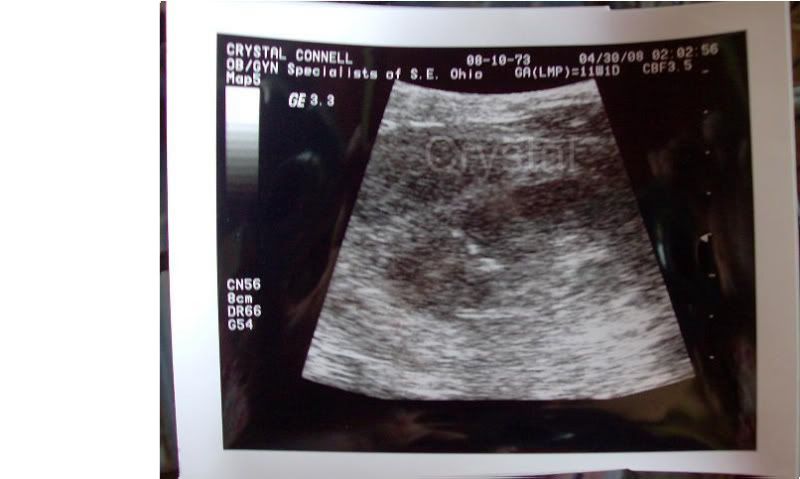

Crystalina wrote: Well I finally got to see my little pea today. He was moving around so much! The doctor started out with what I call the vagi-cam ( ) but he was way too active so he then had to do the belly shot which was much better but the pic had to be magnified so much that it's hard to make him out in it. It was easy when it was live because you just had to keep your eye on the wiggly part of the screen but after he took a still shot it was harder.

He's right in the middle of the shot and his head is on the left side and of course his feet are on the right.

His little heartbeat was 173 which is great and everything looks perfect so far.